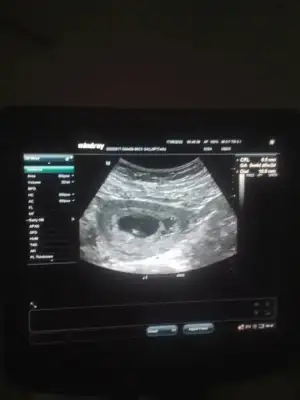

Merhabalar 5+3 karından usgSelam Kızlarbir çok kişi gruplardan beni bilir. Yine yetiştim imdatlara

5 ve 14. haftaya kadar olan ultrason fotolarınızı paylaşın. Vajinadan mı yoksa karından mı çekildiğini ve kaç haftalık olduğunu da mutlaka belirtin.

prenses gibi ama tam ortada emin olamadımBana yorum yapmadın yapablirmisn 7+4 karından

teoriye göre erkek kuzu6. Hafta